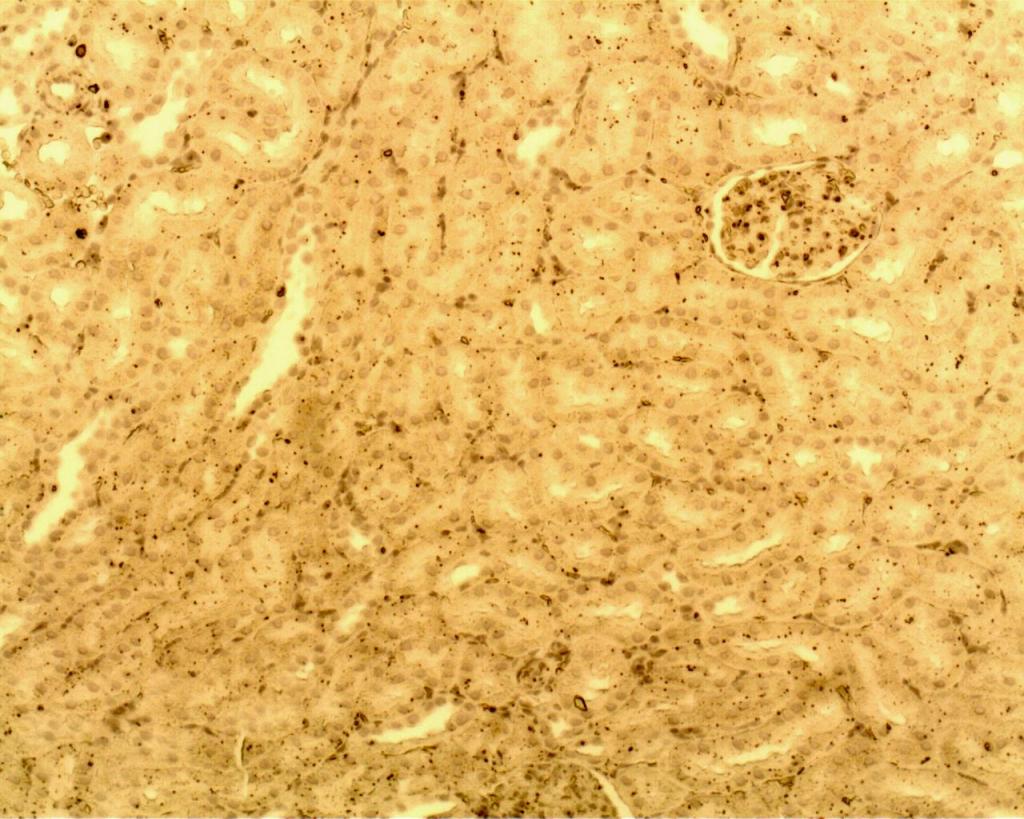

免疫组织化学(IHC)问题求助